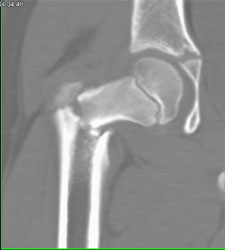

Ewing Sarcoma